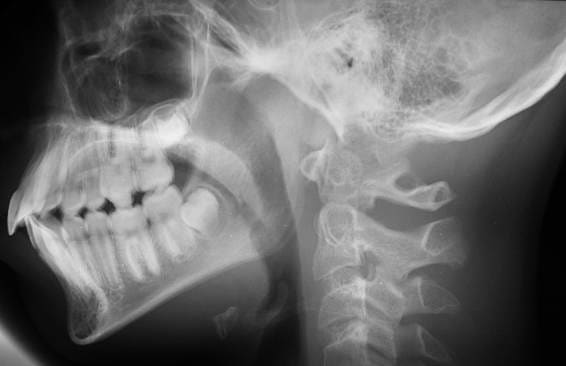

Dans l’immédiat, voici une copie de la télé 2004. Si elle ne convenait pas, je prendrai demain un nouveau cliché de cette téléradio.

ta tele,c'est mieux mais on cherche encore le conduit auditif...

Le diagnostic d'une déglutition infantile ne peut reposer que sur une observation clinique, certainement pas sur un cliché radio. De plus les téléradios sont censées etre prises en PIM, et non en position de repos ou durant la déglutition. Une eventuelle déglutition infantile n'empeche pas de prendre un cliché en occlusion: il y a une erreur du manipulateur radio durant le premier cliché, c'est tout...(tu noteras qu'il n'est pas pris en Francfort horizontal non plus ce premier cliché, deuxième erreur...)

Ok, le point A semble avoir légèrement reculé (les tracés sont-ils fiables?), mais je mesure un ANB de 5,5, valeur d'une cl.II légère, qui correspond d'ailleurs à une cl.II dentaire assez discrète également (apparemment 1/2 cuspide).

dans ce cas je vois aussi une vestibuloversion importante des incisives inferieures ,un ANB tres positif ,un point A tres en avant de la projection Nasion sur Francfort,une difference Co-A - Co-Gn normale,bref on baigne dans la classe I voire II squelettique.

Donc j'ai du mal a switcher sur une prevision de croissance classe III

Tu parles d'une mesure de longueur dans le tableau qui pourrait nous orienter,mais la seule inscrite est celle de la protrusion des Inc Sup=Iu-APO=13,5 mm

Pour les signes d'alerte a la classe III:

L'angle facial( 86)la deflexion cranienne(29-30) ne sortent pas tellement des normes,on ne peut pas les ranger dans des deviations cliniques.

Il y a donc perturbation de la valeur dela longueur de la branche horizontale (tu as mesure 85 sur la derniere tele?)?

La branche montante et le porion qu'il faut situer,franchement je ne le fais jamais,c'est donc tres flou,il va falloir un petit topo pour nous eclairer( si tu n'as pas encore craque?)